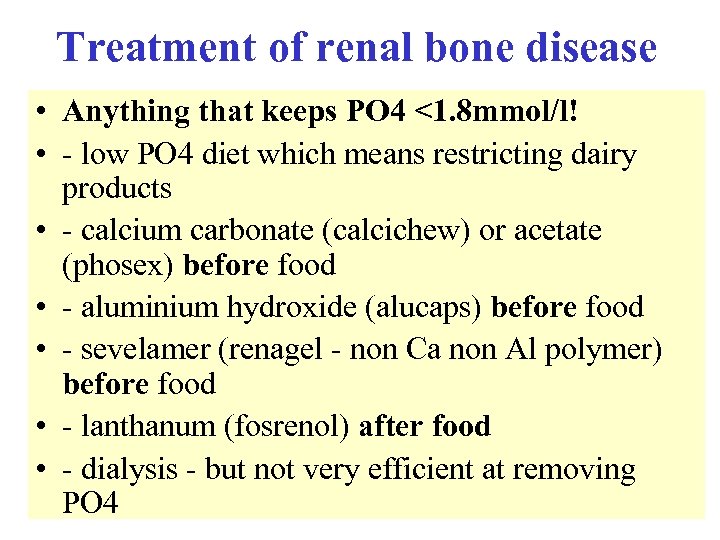

Treatment of renal bone disease • Anything that keeps PO 4 <1. 8 mmol/l! • - low PO 4 diet which means restricting dairy products • - calcium carbonate (calcichew) or acetate (phosex) before food • - aluminium hydroxide (alucaps) before food • - sevelamer (renagel - non Ca non Al polymer) before food • - lanthanum (fosrenol) after food • - dialysis - but not very efficient at removing PO 4

Treatment of renal bone disease • Anything that keeps PO 4 <1. 8 mmol/l! • - low PO 4 diet which means restricting dairy products • - calcium carbonate (calcichew) or acetate (phosex) before food • - aluminium hydroxide (alucaps) before food • - sevelamer (renagel - non Ca non Al polymer) before food • - lanthanum (fosrenol) after food • - dialysis - but not very efficient at removing PO 4

Treatment of renal bone disease • Alfacalcidol or calcitriol (1: 25 DHCC) to keep calcium normal and PTH 2 -4 times ULN after controlling PO 4 • Cinacalcet (Mimpara) for severe 2 y HPT • Parathyroidectomy for 3 y HPT, uncontrollable itch with high Ca-PO 4 product and calciphylaxis (skin necrosis) NB Hypercalcaemia assoc with renal bone disease does not respond to oral steroids and renal osteomalacia does not respond to 25 OHD

Treatment of renal bone disease • Alfacalcidol or calcitriol (1: 25 DHCC) to keep calcium normal and PTH 2 -4 times ULN after controlling PO 4 • Cinacalcet (Mimpara) for severe 2 y HPT • Parathyroidectomy for 3 y HPT, uncontrollable itch with high Ca-PO 4 product and calciphylaxis (skin necrosis) NB Hypercalcaemia assoc with renal bone disease does not respond to oral steroids and renal osteomalacia does not respond to 25 OHD